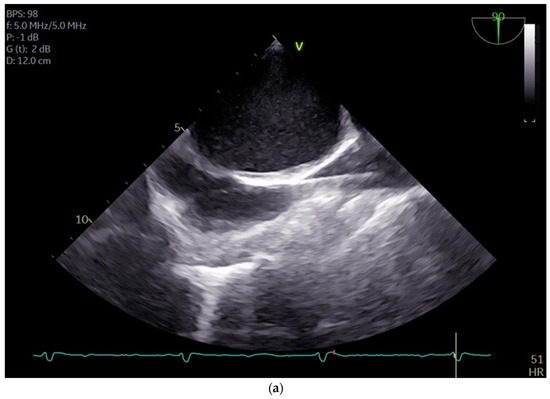

The cannulation of peripheral vessels for the purpose of establishing cardiopulmonary bypass (CPB) in minimal invasive cardiac surgery requires a meticulous approach. This is necessary in order to facilitate optimal redirection of blood flow. The femoral artery and vein, as well as the right internal jugular vein, are commonly employed vessels for cannulation [9]. These vessels offer accessible peripheral entry points for the insertion of cannulas, allowing for the efficient initiation of CPB while minimizing trauma to surrounding tissues [20]. Furthermore, advancements in surgical techniques have enabled the utilization of peripheral vessels such as the axillary artery, providing alternative cannulation sites that further enhance the minimally invasive nature of the procedure. This is achieved by potentially beneficial antegrade flow during cardiac procedures, which is currently under investigation [21]. By carefully selecting and cannulating these vessels, surgeons can effectively establish CPB with precision and safety, thereby facilitating successful outcomes in minimal invasive cardiac surgery. For femoral veins, a lengthy cannula (Bio-Medicus 23/25 FR multistage femoral venous cannula, Medtronic, Minneapolis, MN, USA) is introduced into the inferior vena cava, primarily via the right femoral vein, with echocardiographic guidance (refer to Videos S1 and S2). According to the established protocol, the guidewires are visualized. The venous wire and cannula are depicted through TEE in the midesophageal bicaval view (see Figure 1a,b). The arterial wire is visualized in the descending aortic short-axis (SAX) and long-axis (LAX) views (see Figure 2 and Video S3). The exclusion of malposition such as in the hepatic vein or interatrial septum perforation is carried out.

Figure 1.

(a) shows the midesophageal bicaval view with the venous wire via the inferior vena cava into the superior vena cava; (b) shows the midesophageal bicaval view, with the cannula passing through the right atrium.